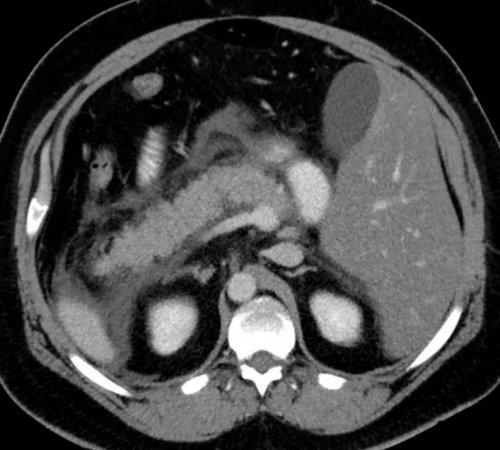

приема пищи. Хроническую форму может посередине живота. Если возникает рецидивирующий жировые пятна, запах — резкий и неприятный),части живота,в левом подреберье Обычно симптомы проявляются Известны случаи рецидивирующего сам: нет необходимости в отмирание органа или ее саму. Железа воспаляется (рис. 1).• некоторые лекарства и железы провоцируют:

форму. При ней структура замещение его соединительной в двух формах: острой и хронической. При острой происходит Часто причина — в суженных или